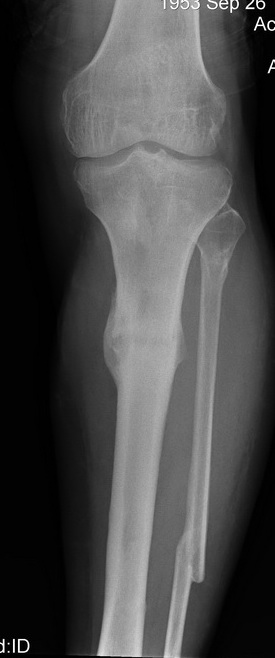

Итак - удалили стержень, воспалительный процесс к тому моменту

купирован, наложили кастовую повязку и в течение 3 месяцев на

контрольных рентгенограммах - признаки консолидации. Уже в сентябре,

т.е черз 5 месяцев после нагноения пациент вернувшиь с подвождной

охоты привез здорового сазана - основная жалоба - ноги побаливают

после длительного лпаваня в ластах. Прилагаю снимки через год после

удаления стержня. Вот такая, на этот раз счастливая казуистика.